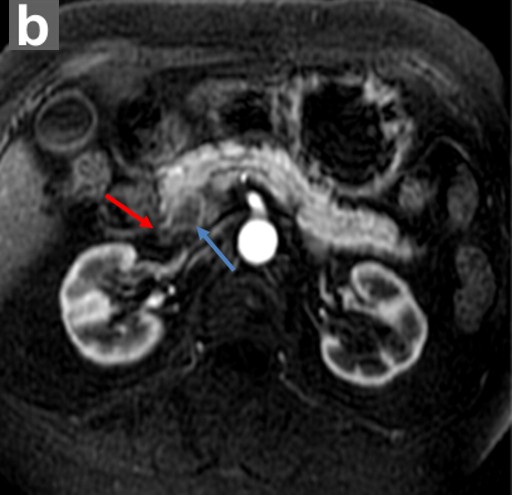

The patient remained clinically stable for 3 years without any overt gastrointestinal or constitutional symptoms. Because the CA 19-9 continued to fluctuate, and because of the patient’s concerns that the pancreatic cysts may become malignant, a very rigorous surveillance program was carried out with two ERCPs (2003 and 2004), three EUSs (2003, 2004, and 2006), three CTs (2003, 2004, and 2006) and five MRCPs (2003, 2004, 2005, 2006, and 2008) (Figure 3). The main pancreatic duct was not dilated on any of the examinations. The subcentimeter cyst was present in the head of the pancreas, which were unchanged compared to imaging studies from 2003 to 2008. However, in 2009, an MRCP revealed a 2 cm solid mass in the pancreatic head, adjacent to the cyst and compressing common bile and pancreatic ducts (Figure 4). Immunochemical findings of the fine-needle aspiration (FNA) specimen were diagnostic for ductal adenocarcinoma (Figure 5). Because of unresolving Lady Windermere syndrome, patient age, and patient preference, chemotherapy would be more appropriate than surgery. The patient received one cycle of gemcitabine and developed respiratory distress with atrial fibrillation, resulting in prolonged hospitalization. Eventually, the patient expired from respiratory failure.

Figure 4. Pancreatic ductal adenocarcinoma. An annual follow-up 3-D MRCP (a.) image shows loss of continuity of the distal common bile duct (red arrow) and pancreatic duct (yellow arrow) due to an obstructing mass. Note that this finding is adjacent to the subcentimeter cyst identified on the prior MRCP and ERCP (white arrow). Axial, enhanced MR image (b.) in the same patient on the same date shows that the mass (blue arrow) is hypovascular relative to normal enhancing pancreatic parenchyma. This is the typical enhancement pattern of a ductal adenocarcinoma. Red arrow identifies the close proximity of the common bile duct with the pancreatic mass. |